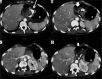

Material and methods: We retrospectively review 954 obese patients who underwent bariatric surgery between 2013 and 2019. The study included 72 patients who developed clinical suspicion of acute complications (painful and meteoric abdomen, nausea, vomiting, fever, intestinal blockage) within 6 days of bariatric surgery of sleeve gastrectomy, gastric banding, gastric bypass with Roux loop confirmed by CT, and who underwent a gastrointestinal transit before the CT examination.

Results: GI exam allowed visualisation of 58% of complications. Analysing the data for each surgical technique, 46 post-operative complications were found involve gastric banding. The most frequent was bandage migration (26 cases, 56 %), identified in all cases at GI transit and then confirmed on CT.